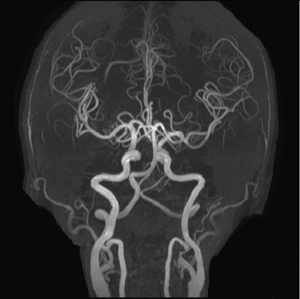

●症例7 脳血管障害疑い(85歳,女性)

成人のMRAでは,頭蓋内から頸部までの撮像が必要な場合も多いが,このような広範囲のMRAでも,細部まで評価可能な画像が得られている。

MRA,TR/TE:22/3.91,マトリックス:1024×768,撮像時間:13分36秒